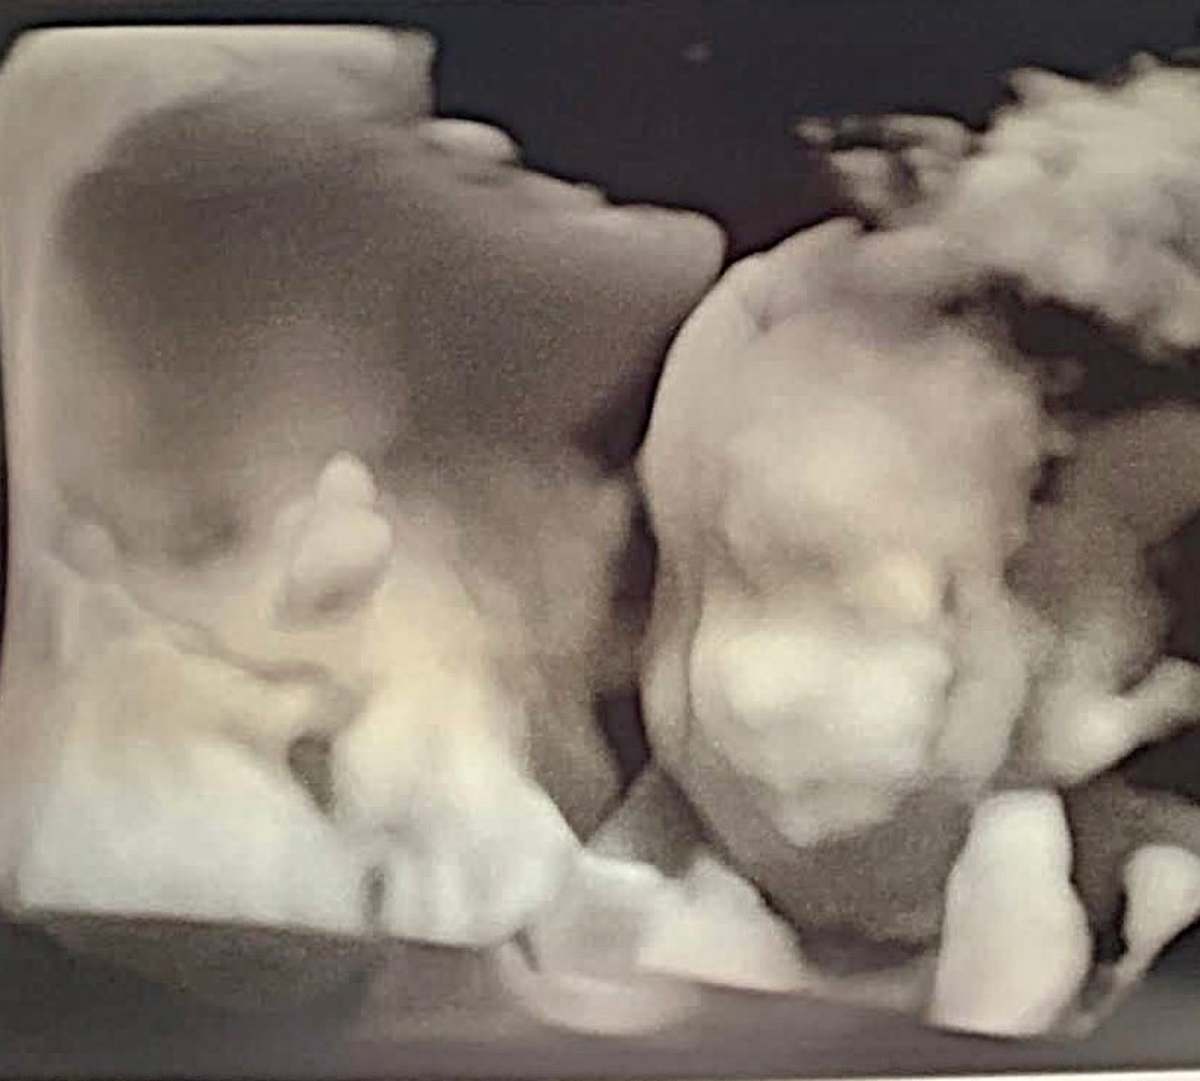

Life, it seems, has been scripting its own gothic tale for me. A new little soul is on the way—a baby girl, due January 2026. She will be my third child, a fresh chapter I both cherish and fear in equal measure. But this haunting is not without trials. This pregnancy is high risk, a story marked with hospital visits, morning sickness that feels like a curse, and blood thinners for a DVT lurking in my right leg like an unwelcome phantom.